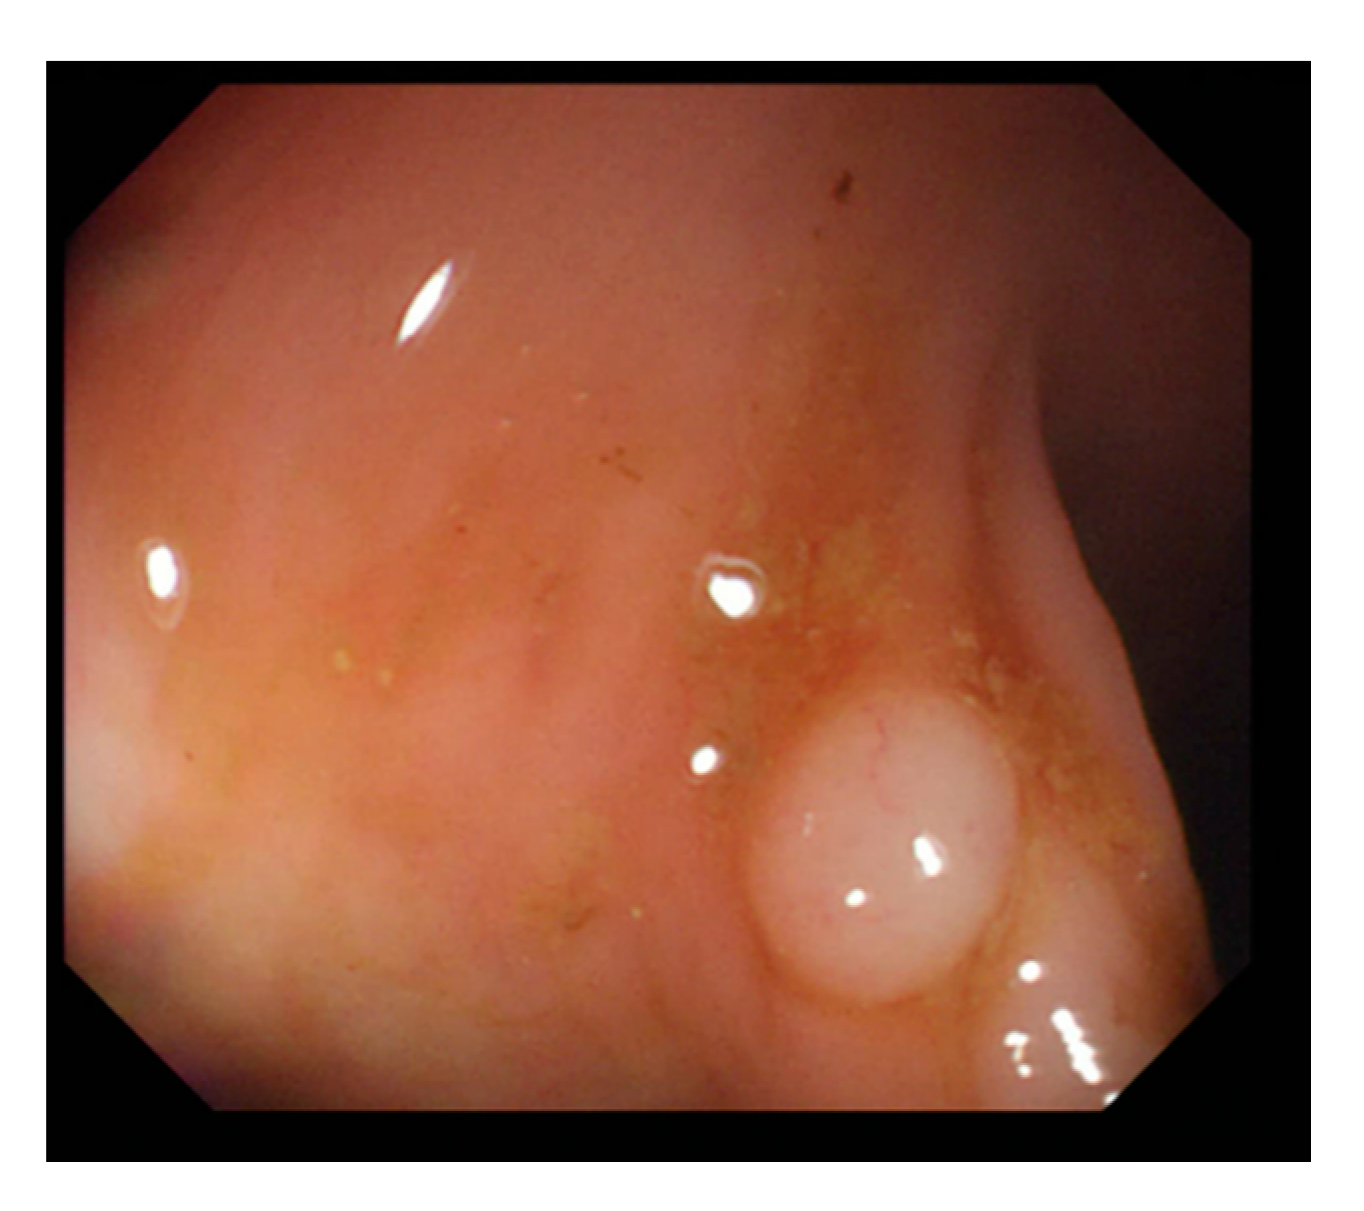

Currently, many medical images are processed into grayscale images, such as ultrasound, computed tomography (CT), and magnetic resonance (MR) images. Tan et al. [44] applied a gray-level cooccurrence matrix and CNN to CT images for polyp diagnosis. Zhang et al. [45] compress the three-channel color images of chest CT to grayscale images. A five-layer deep CNN with stochastic pooling is used to diagnose chest-based COVID-19. Xie et al. [46] mentioned that in deep learning, colors are not the key features influencing accurate image classification. They also discovered that in X-ray image classification, the speed and accuracy of processing grayscale images were considerably higher than those of processing RGB images. The grayscale method used was ITU-R Recommendation BT.601 [47]. Moreover, misjudgments were easily made in the presence of excessive intestinal wall textures, when polyps were too small (Figure 2), and when polyp textures were similar (Figure 3) to intestinal wall textures.

Figure 3. Small texture of polyp and intestinal wall.